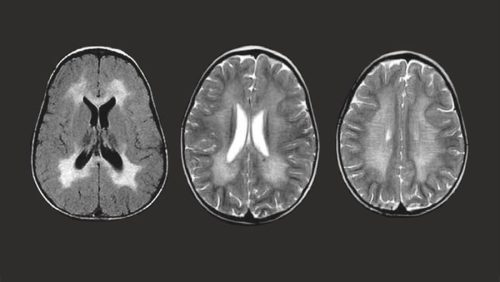

Laman resmi Children’s Hospital of Pittsburgh menjelaskan MLD merupakan penyakit yang ditularkan dari orang tua ke anak melalui gen yang rusak. Cleveland Clinic menuliskan kondisi tersebut menyebabkan kerusakan pada otak dan sumsum tulang belakang serta saraf tepi.

Tubuh tidak bisa memproduksi enzim arilsulfatase A dengan baik pada mereka penderita MLD. Keadaan ini membuat mielin, lapisan khusus pelindung saraf tubuh menghilang yang akan membuat saraf berhenti bekerja.